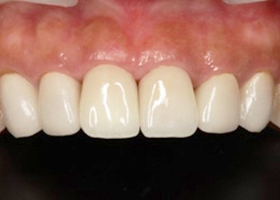

8. 術後口內特寫

proimages/case/cosmetic/pic_case-031.jpg

proimages/case/cosmetic/pic_case-032.jpg